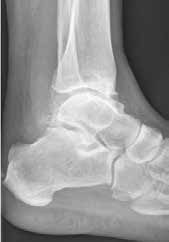

Weiterhin führen Fehlstellungen im Rückfuß zu statischen und dynamischen Überlastungen, da sich bei Varusfehlstellung (Abb. 2a) das Zentrum der Kraftübertragung nach medial und bei Valgusfehlstellungen nach lateral verlagert 47. Die Achillessehne wirkt durch ihren Zug zusätzlich invertierend bei Varusfehlstellung und evertierend bei Valgusfehlstellung auf den Rückfuß ein 48. Möglichkeiten der operativen Therapie sind entweder die einfache Umstellungsosteotomie der distalen Tibia und Fibula als rein supramalleoläre Osteotomie mit dem Ziel einer Überkorrektur des distalen Tibiagelenkflächenwinkels von 3 bis 5° 49 oder die kombinierte Osteotomie an Bein und Rückfuß (Abb. 2b) mit oder ohne Weichteileingriff je nach Topographie der Achsfehlstellung 50. Weitere Möglichkeiten sind die Calcaneusosteotomie, meist als ergänzende Osteotomie nach Wiederherstellung der korrekten Achse (Abb. 2b) im Sinne einer Verschiebeosteotomie, um die Zugrichtung der Achillessehne zu zentrieren, und die Osteotomie der medialen Säule, die bei durch Valgusfehlstellung induzierter Abflachung des medialen Längsgewölbes indiziert sind. Hierbei werden zusätzlich korrigierende Arthrodesen des I. Strahls (Naviculo-cuneiforme-Gelenk, Tarsometatarsalgelenk) oder plantarflektierende Osteotomien (Cuneiforme I oder Metatarsale I) durchgeführt 51.

In ausgeprägten Fällen von Arthrose, oft mit Instabilität im oberen Sprunggelenk (Abb. 7), schwerwiegendem Funktionsverlust und starker Schmerzausprägung, ist nach wie vor die Arthrodese die Therapieoption der Wahl. Dadurch sollen die Achskongruenz wiederhergestellt und die Schmerzen eliminiert werden. Gleichzeitig bedeutet dieser Schritt jedoch, dass keine weitere operative Eskalation mehr möglich ist. Meist kommen die tibiotarsale oder tibiatalar-calcaneare Arthrodese zum Einsatz. Entscheidend für die Wahl des Arthrodeseverfahrens sind der Schweregrad der degenerativen Gelenkveränderungen, der Schmerz und die Stellungsverhältnisse im Subtalargelenk.

Arthrodese